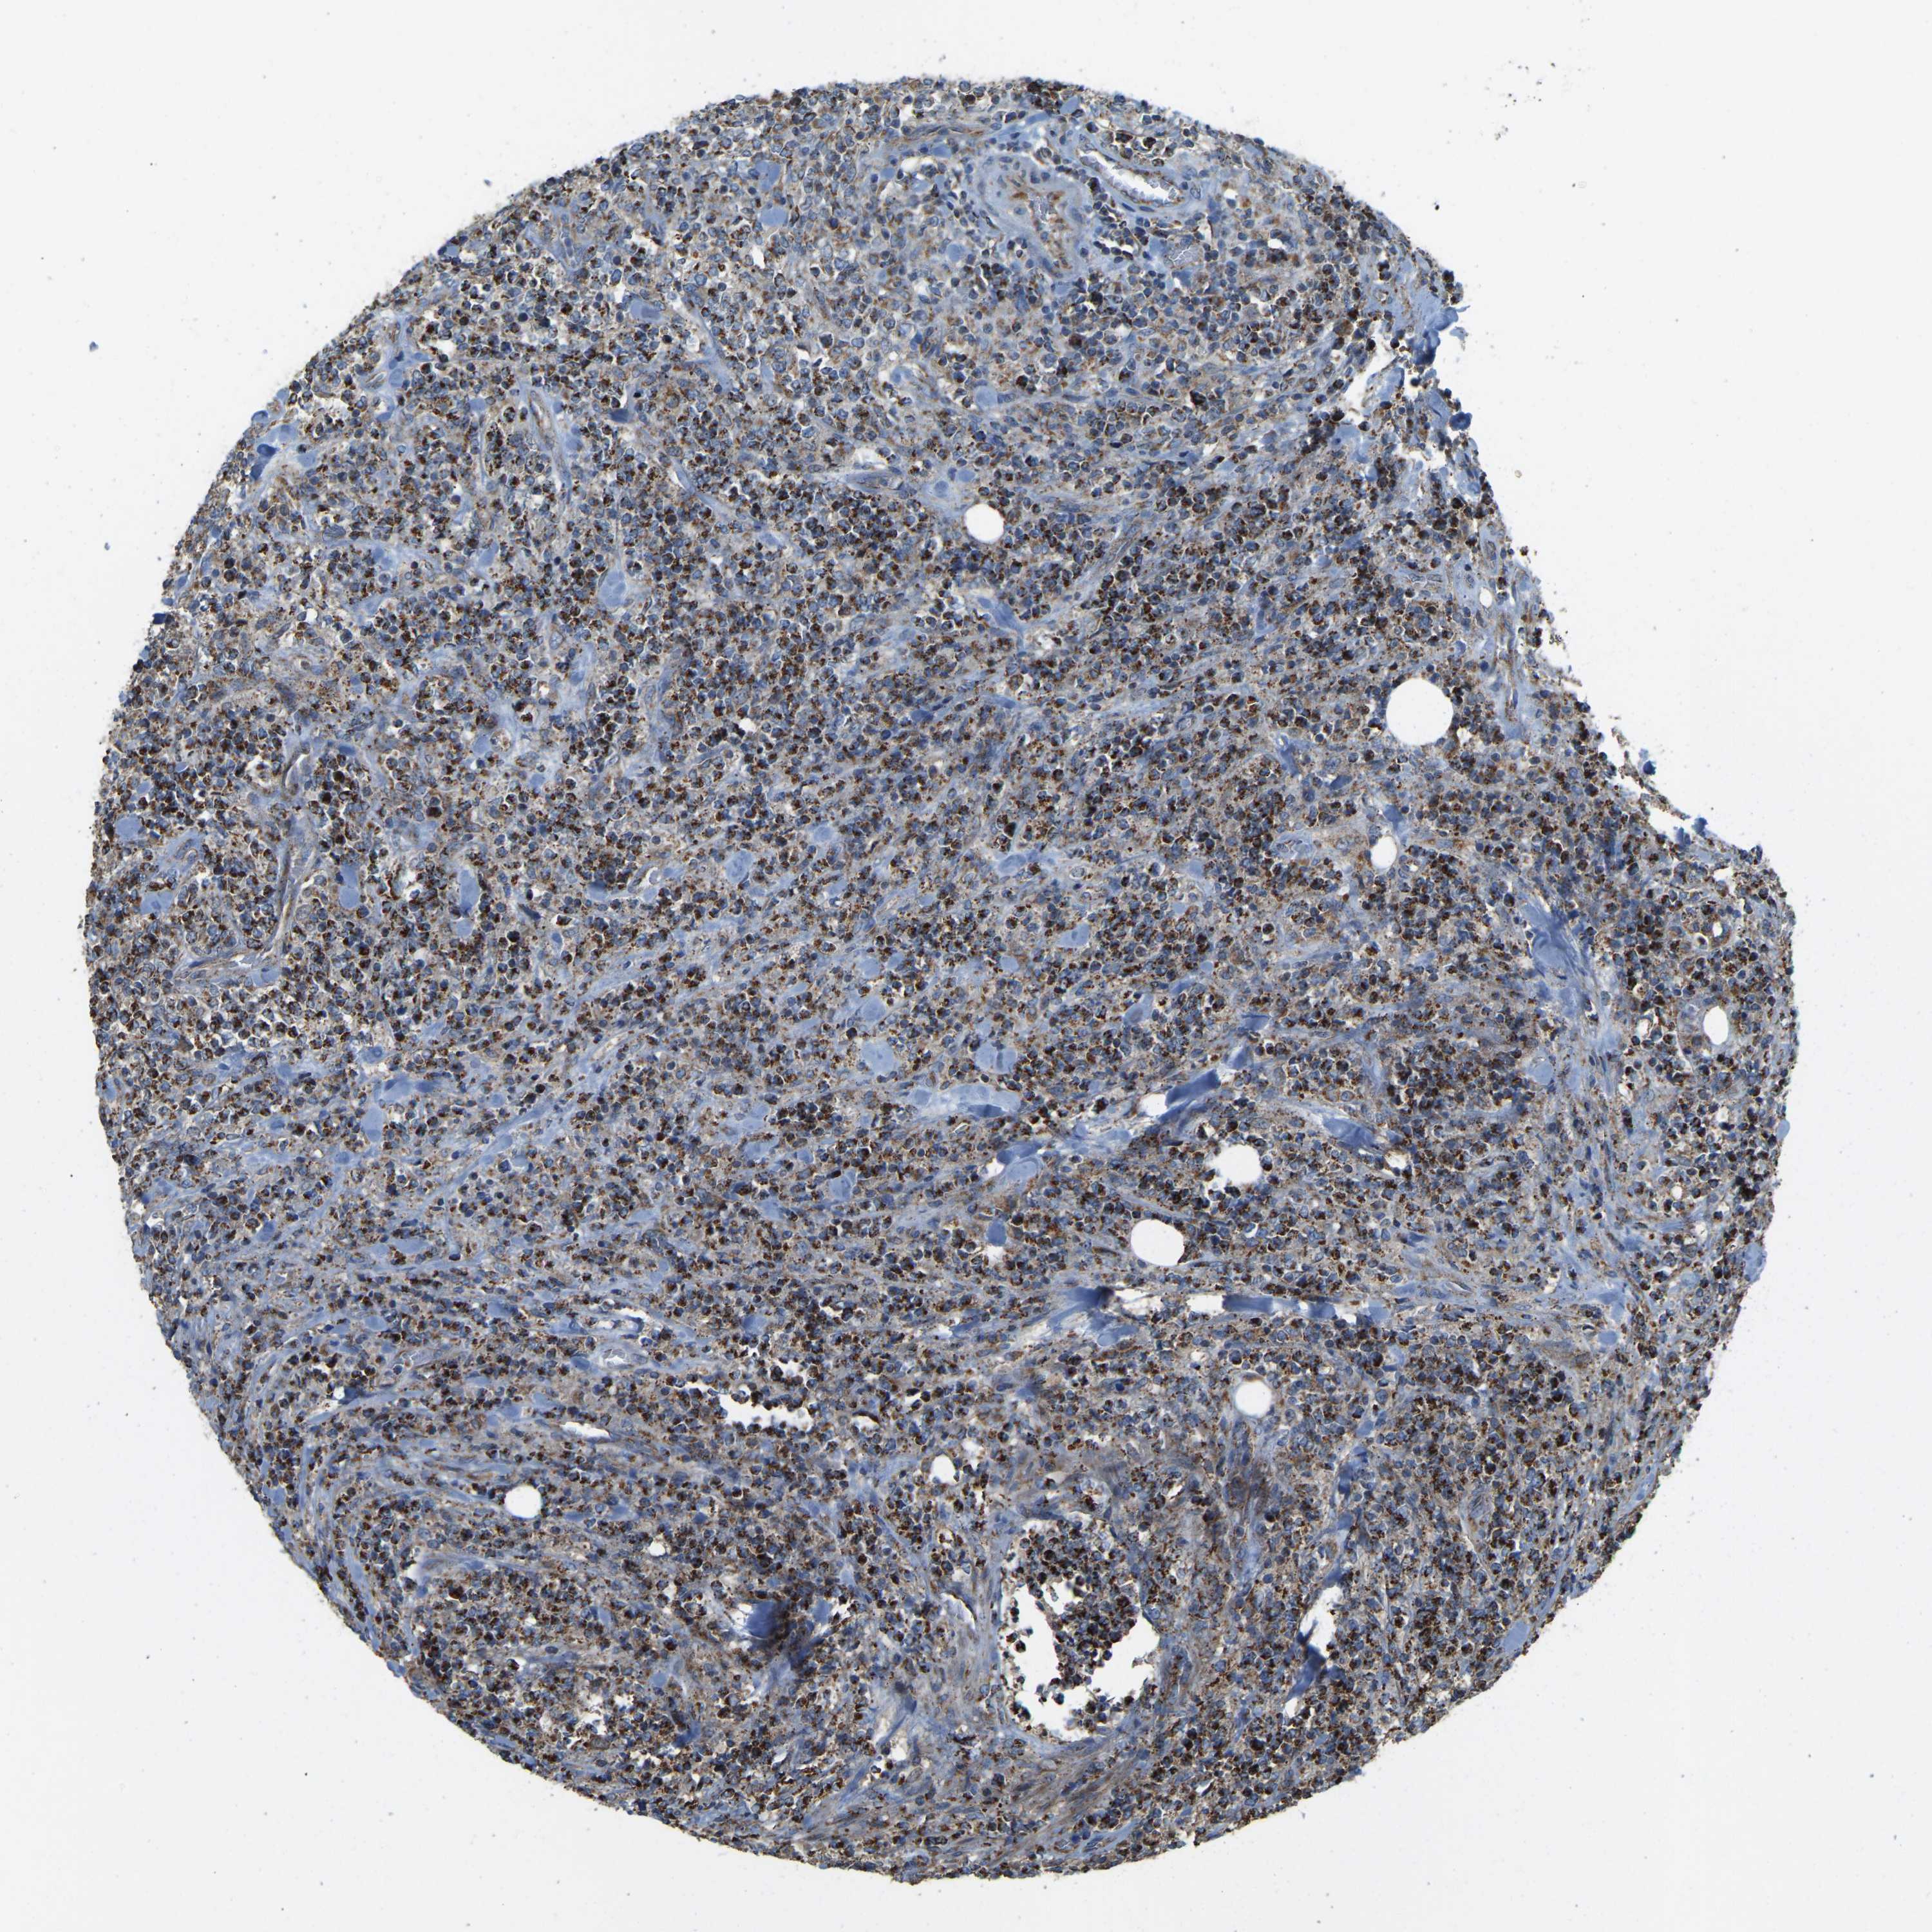

LYMPHOMA - Protein expressioni

A mouse-over function shows sample information and annotation data. Click on an image to view it in a full screen mode. Samples can be filtered based on level of antibody staining by selecting one or several of the following categories: high, medium, low and not detected. The assay and annotation is described here.

Antibody staining in the annotated cell types in the current human tissue is reported as not detected, low, medium, or high, based on conventional immunohistochemistry profiling in selected tissues. This score is based on the combination of the staining intensity and fraction of stained cells.

Each image is clickable and will lead to virtual microscopy that enables deeper exploration of all samples and also displays staining intensity scores, fraction scores and subcellular localization as well as patient and tissue information for each sample.

Antibody HPA049824

Staining

High

Medium

Low

Not detected

Intensity

Strong

Moderate

Weak

Negative

Quantity

>75%

75%-25%

<25%

None

Location

Nuclear

Cytoplasmic/membranous

Cytoplasmic/membranous,nuclear

Malignant lymphoma, non-Hodgkin's type, Low grade

Malignant lymphoma, non-Hodgkin's type, High grade

Hodgkin's disease, NOS